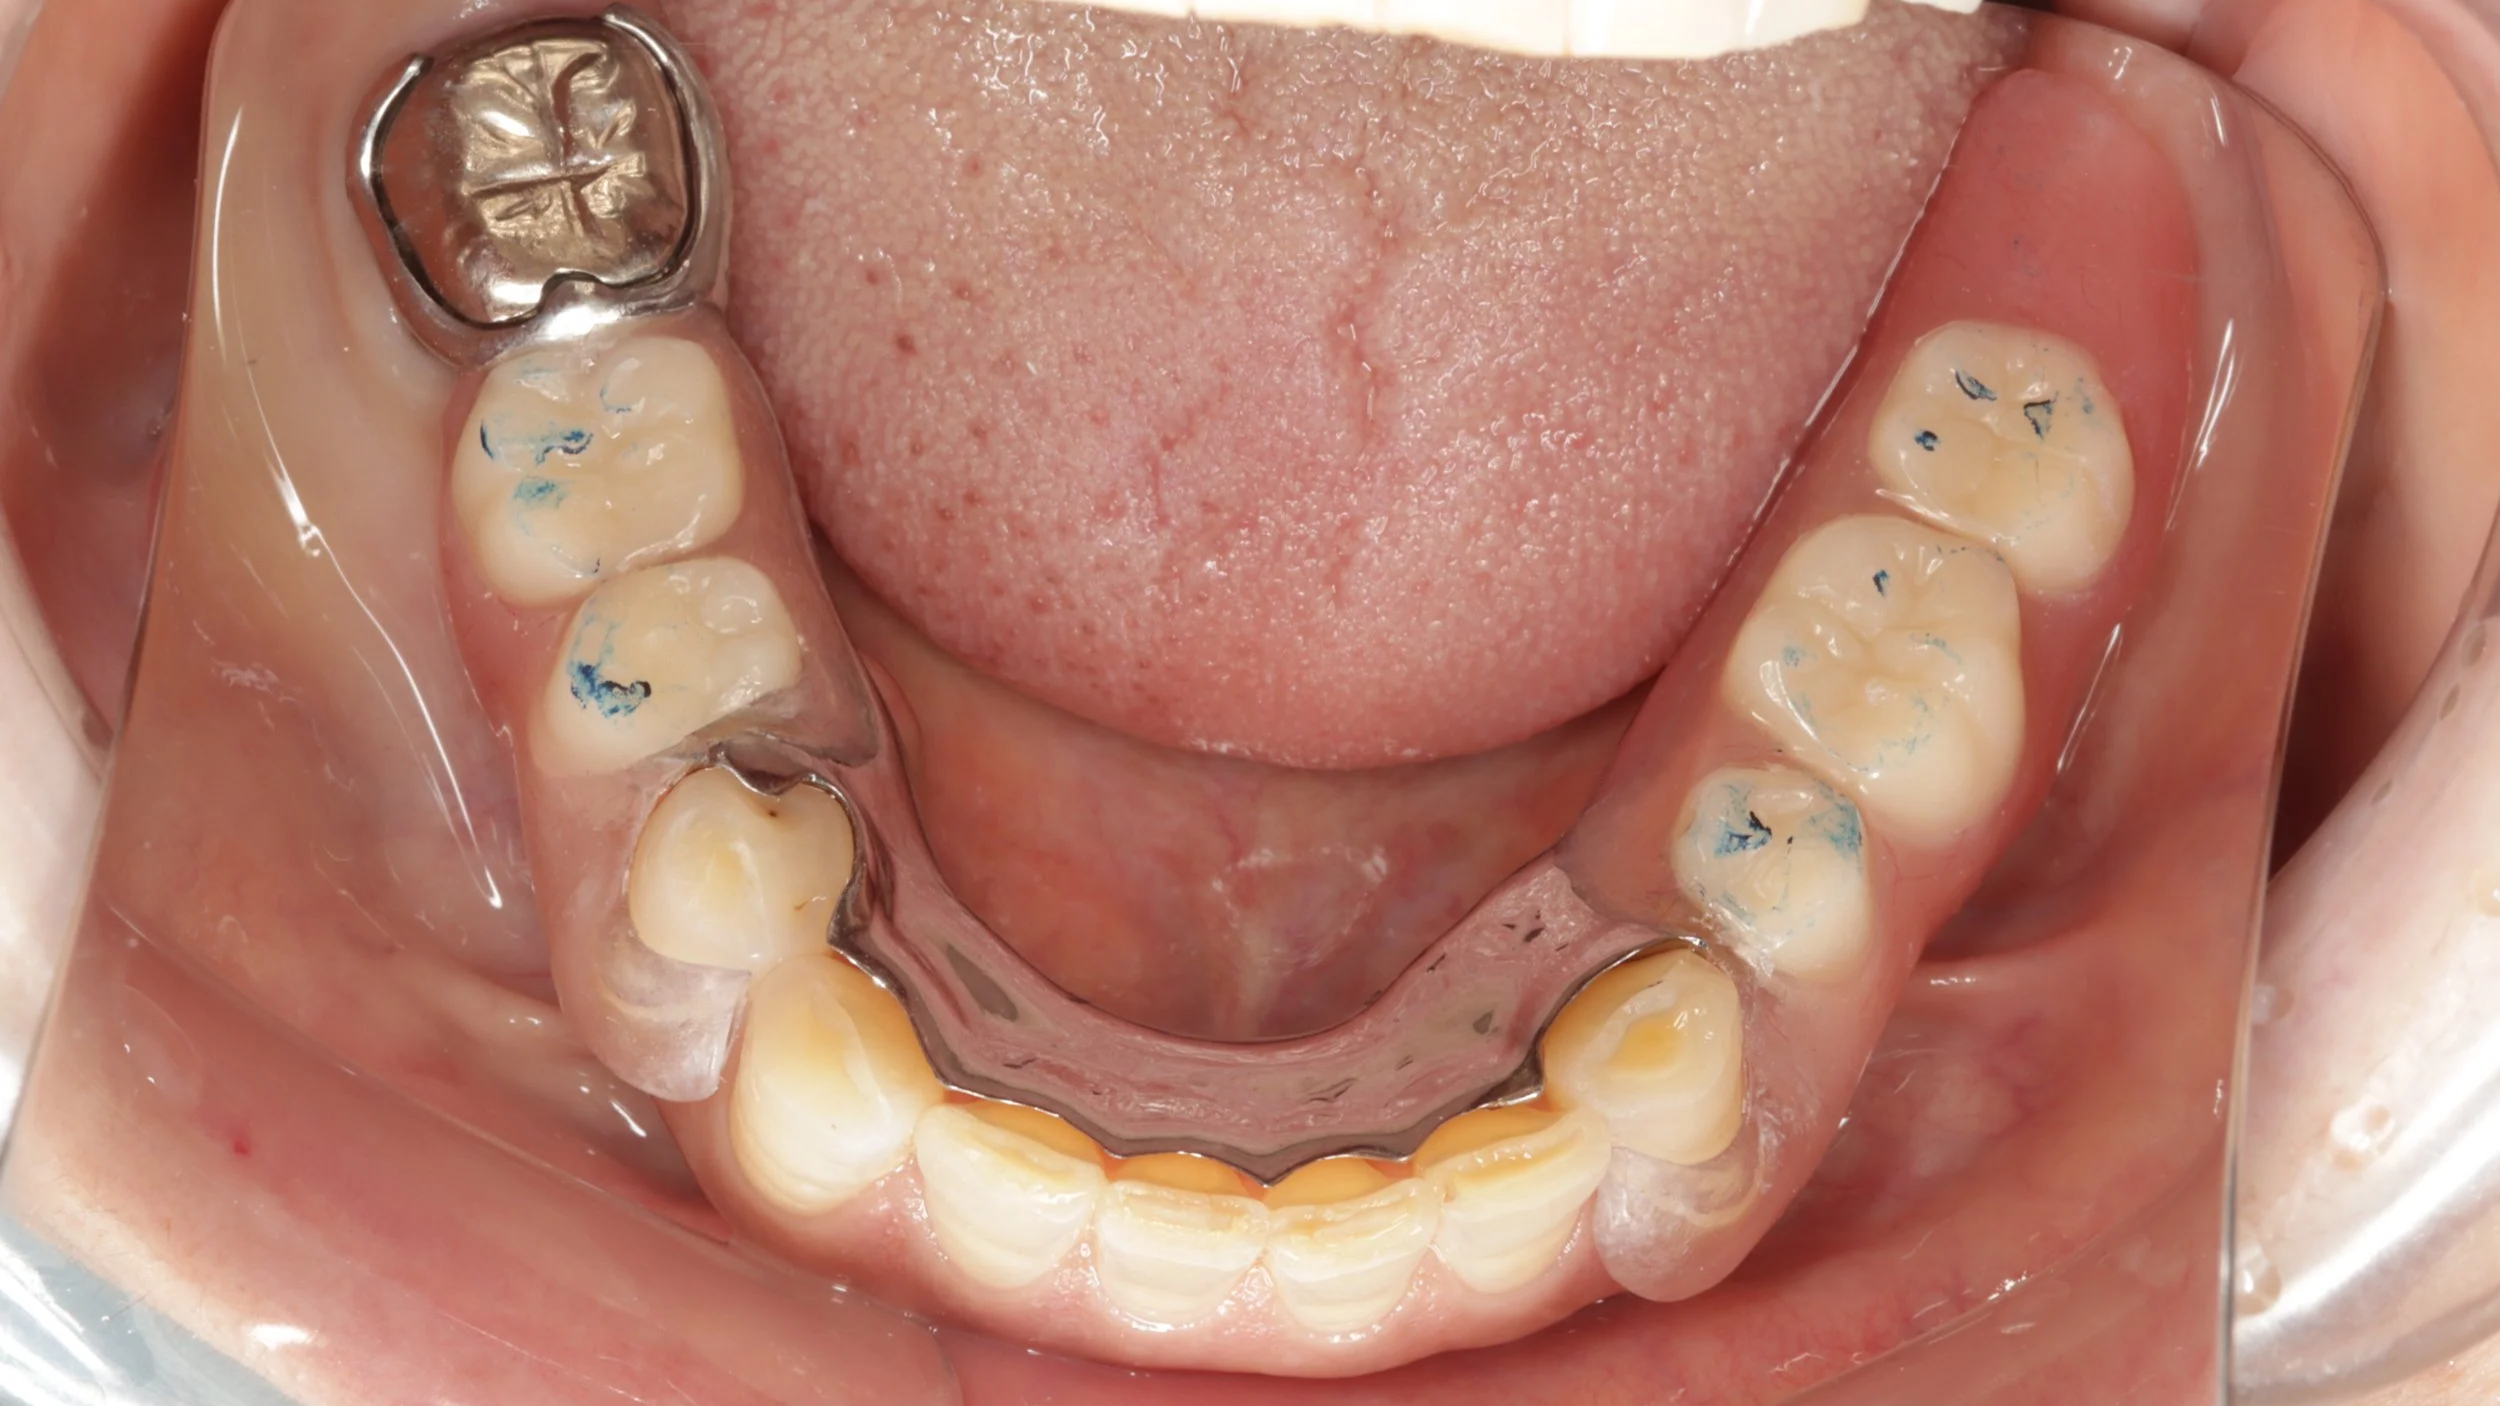

残せる歯は、しっかり根の治療を開始しつつ、新しい入れ歯を装着。内側を金属で薄く作る事で違和感の軽減を図りました。

デジタルデンチャー

内側を金属で薄く作る事で違和感の軽減を図りました。前歯の見える部分は、透明の素材を使用。口の状態によってピンク色のときもあります。